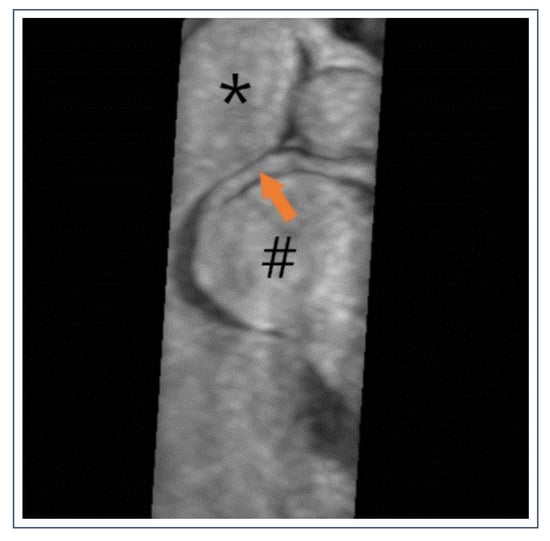

5.6. Anomalies of the Coronary Artery Origin